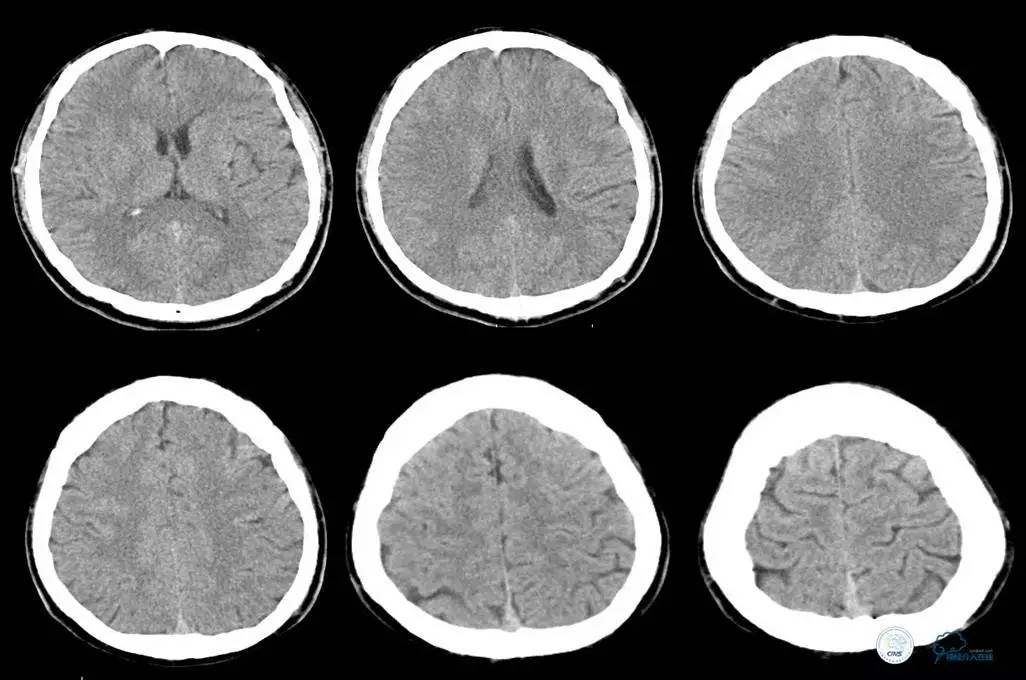

▼主动脉全程CT

诊断:

主动脉夹层 DeBakey Ⅰ型

短暂性脑缺血发作

急性心肌缺血

急性肾功能不全

急性肠系膜动脉缺血

中间诊断:

主动脉夹层 De Bakey Ⅰ型